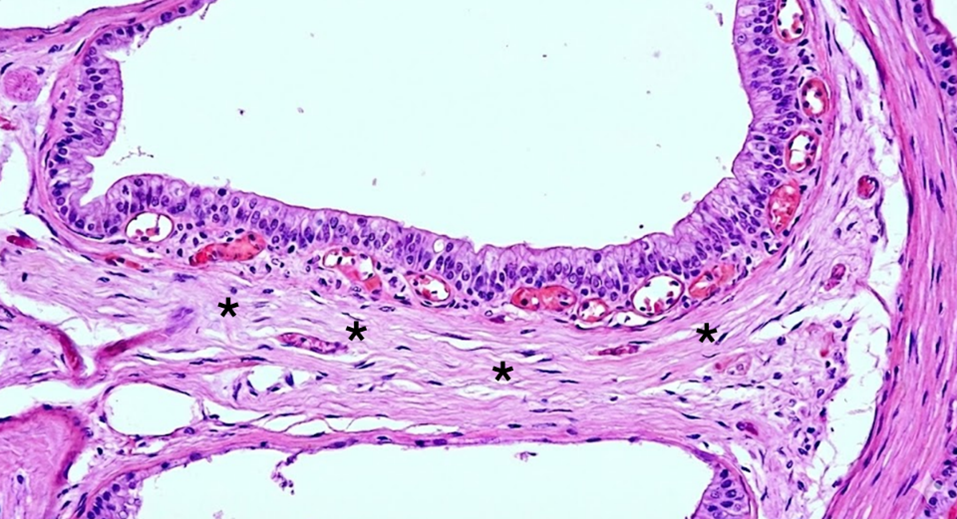

2.114 In der histologischen Abbildung ist eine Schicht zu erkennen, die der knöchernen Wand der Schnecke direkt anliegt. Auf welche Struktur wird hier mit einem schwarzen Stern verwiesen?

- (A) Lig. spirale

- (B) Stria vascularis

- (C) Membrana vestibularis

- (D) Organon spirale

- (E) Limbus spiralis